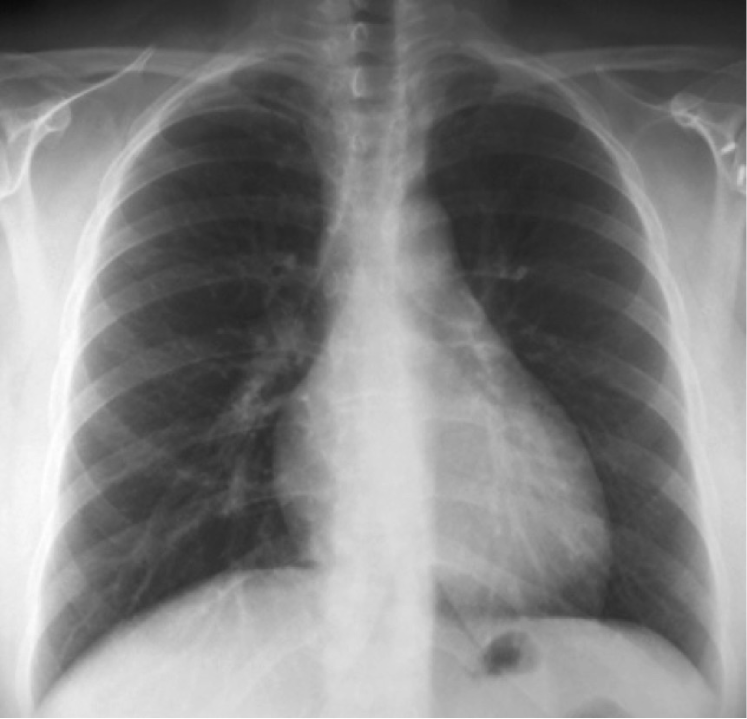

Refer to caption

(a) P-A

(b) Lateral

(c) Lordotic

(d) A-P supine

(e) A-P

(f) P-A

(g) Lateral

(h) Lordotic

(i) A-P supine

(j) A-P

Figure 2: Common chest x-ray projections.

The projection information is highly relevant for diagnosis. For example, AP views, which are commonly used in pediatric patients, show an enlarged heart silhouette (Fig. 2(j)) that should not be interpreted as cardiomegaly, but merely the expected large-depth ratio of reversed organ observation (Fig. 3). Another illustrative example is the distinct pattern that pleural effusions have in the standing position (Fig. 4(a)), in which a typical meniscus sign is commonly found as opposed to decubit projections (Fig. 4(b)). Given that the number of different projections is unbalanced (for instance, PA followed by lateral projections typically comprise the majority of chest x-rays), there is the risk that none of the other projections will have sufficient instances with which to train models capable of discriminating pathological from non-pathological patterns in the context of the projection.

There are particular radiological landmarks that differentiate projections, which radiologists are trained to identify. For instance, in the case of PA projections, these landmarks are the presence of air in the gastric chamber and the scapulae projected outside the lung fields. Although these features can be learned, models trained in unbalanced datasets with a poor representation for different projections may not have sufficient instances to properly learn those patterns. An illustrative example is when the heart enlargement in AP projections is attributable only to the effect of the projection, while the trained model erroneously predicts cardiomegaly.